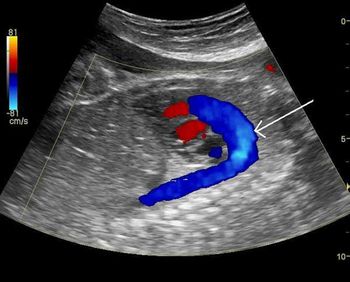

Challenge your diagnostic skills: Can you identify this structure in the fetal thorax?